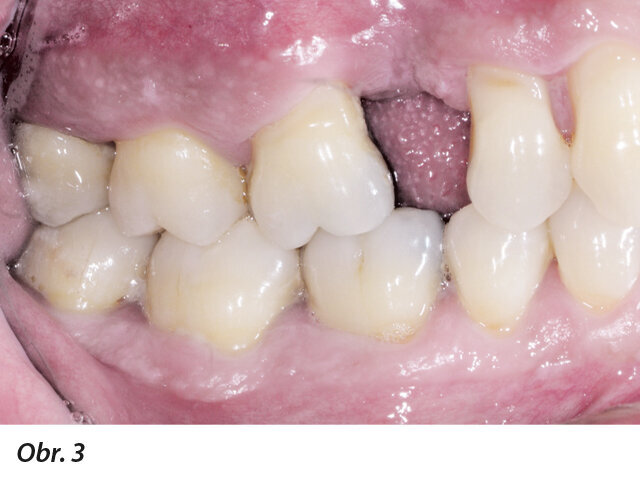

Obr. 1–5: Fotografi cká dokumentace počátečního stavu před parodontologickým ošetřením

49letý pacient přišel na naše oddělení se stížností na krvácení dásní a rozestupování frontálních zubů (obr. 1–5).